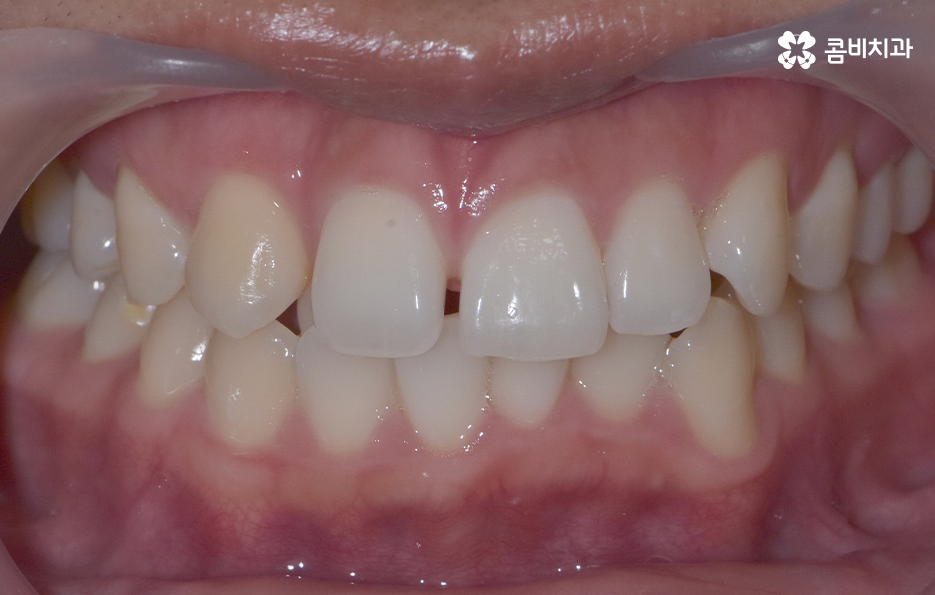

덧니가 나는 원인은 유전적인 영향부터 골격적인 부분 등 다양하지만 기본적으로는 치아가 나올 공간이 부족해서 덧니의 형태로 영구치가 자라는 경우가 많기 때문에 덧니 교정 사례에는 유독 발치 교정 사례가 많이 있는데요

요즘은 앞니만 약간 벌어져도 교정을 하는 분들이 크게 늘고 있기 때문에 덧니가 심하지 않아도 교정을 하는 분들도 많기 때문에 덧니 교정 사례에서도 비발치 사례도 많지만 보편적으로 덧니 발치교정 사례가 많은 것도 사실이기 때문에 어떠한 경우에는 발치교정이 필요하며 또한 어떻게 치아교정 계획을 세우는 것이 좋을지 오늘 포스팅에서 알아볼 거예요

다만 덧니 교정 사례에서 발치교정 사례가 많은 이유는 턱뼈가 좁아서 치아가 덧니로 자란 경우가 많기 때문에 치열을 재배열하기 위해서는 치아가 움직일 수 있는 충분한 이동공간이 필요하기 때문에 공간 확보의 목적으로서 작은 어금니 양옆, 위아래 4개를 발치를 하는 발치교정법이 보편적으로 많이 활용되고 있으며 치아의 이동 공간을 확보하는 방법으로는 발치 교정법 외에도 악궁확장, 어금니 후방이동, 치간삭제와 같은 비발치적인 방법도 가능하기 때문에 치아를 얼마나 이동시켜야 할지에 따라서 치료법은 개인차가 발생되고 있어요